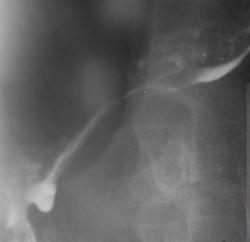

Иллюстрация 1. Пищевод обычного расположения, хорошо контрастирован в верхней и средней трети за счет резкого «эксцентрического» сужения просвета пищевода в нижней трети грудного отдела. Контрастная взвесь тонкой струйкой «распределяется» по патологически измененному участку пищевода.